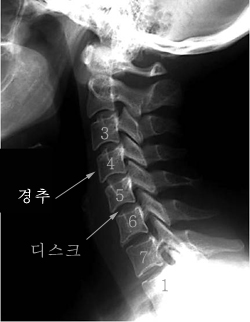

목디스크는 목 쪽 척추인 경추와 경추 사이에 위치한 추간판 사이로 내부의 수핵이 빠져나와서 신경근 또는 척수를 누르는 질환이며 목디스크의 정확한 명칭은 경추 추간판 탈출증이라고 합니다. 잦은 휴대폰 사용과 함께 업무를 볼 때 자연스럽게 구부정한 자세로 앉아 있다 보니 이로 인해 목디스크 증상까지 동반되는 경우가 많다고 합니다. 목디스크는 오랜 시간 축척된 경추 관절 및 디스크의 퇴행성 변화가 원인입니다.